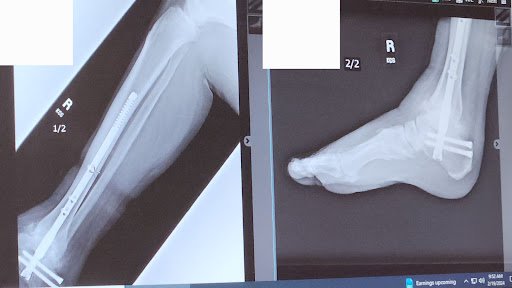

February 12, 2024I broke my ankle while on vacation in Massachusetts. I was lucky to get an appointment with Dr. Hegewald soon after we returned to Portland. Dr. Hegewald is confident, decisive, smart, and caring. Everyone I have dealt with in his office has been wonderful. Less than 3 months after my... read more surgery I am walking again, which exceeded my expectations. I am very thankful to have had Dr. Hegewald in charge of my care.

June 3, 2025Dr. Hegewald was the surgeon who repaired my left ankle dislocation and fracture after a nasty fall. Six months later I am back to hiking and biking and expect to make a full recovery. He and his team were easy to work with and answered all of my questions.